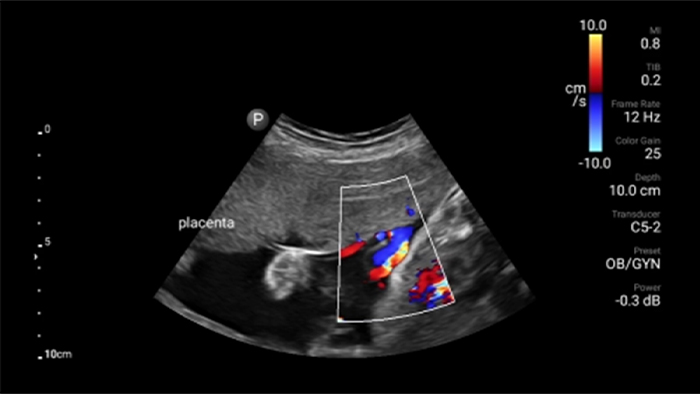

Disminuya las complicaciones de las inserciones de CVC

La guía por ultrasonido en tiempo real puede mejorar la precisión y la seguridad de las inserciones de CVC.